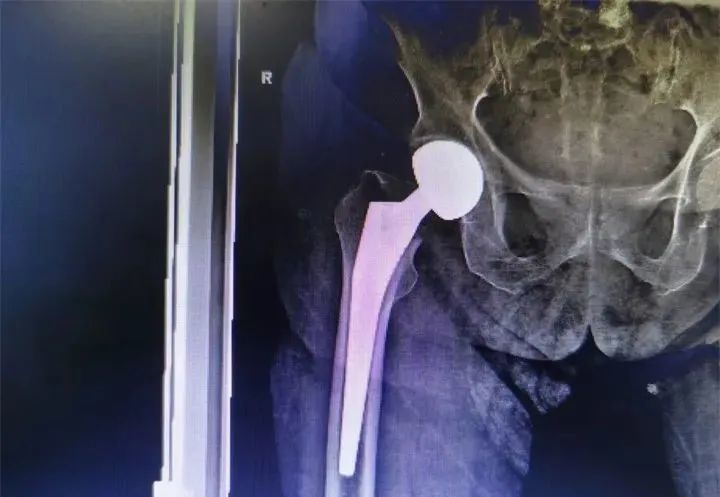

“入院后经相关检查提示严奶奶是‘右股骨颈骨折’,如果采用保守治疗,老人将会面临长期卧床、疼痛、褥疮、坠积性肺炎、深静脉栓塞等一系列并发症,严重影响生活质量甚至生命安全。”骨科黄才智医生介绍道,当时骨科医生一致认为帮助老人解决问题的最佳方案是人工股骨头置换术。

在麻醉科协助下,骨科专家团队为老人进行了右侧人工股骨头置换术,手术在45分钟内完成,手术过程顺利。返回病房后,护理团队耐心协助病人翻身,指导术后功能锻炼。